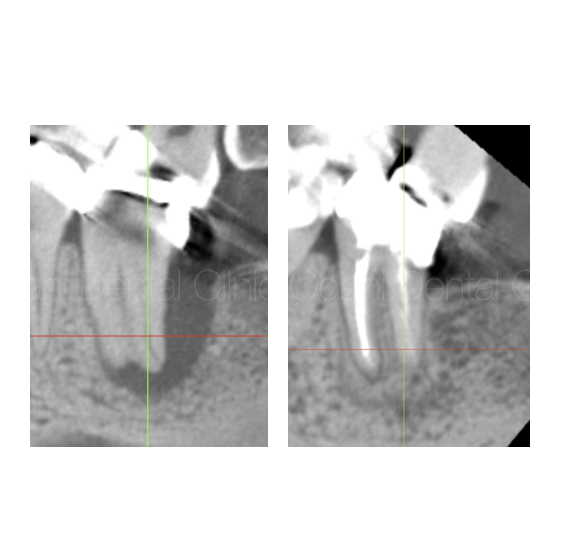

診察および画像検査の結果、歯の周囲に黒い影(赤丸)が確認できました。

CT画像を頼りに、30倍まで拡大できる歯科用マイクロスコープ下で根管を探索していきました。

すると、隠れた4本目の根管(黄色の点線部)が発見されました。